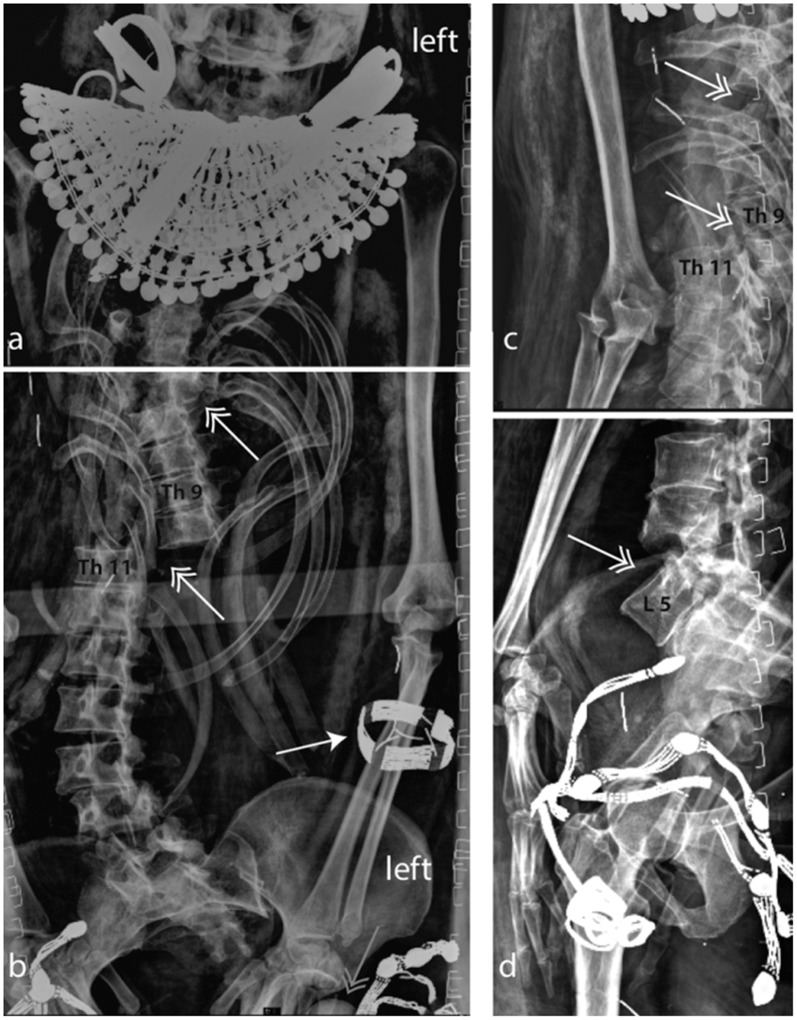

La funzione apotropaica di questi oggetti emerge da questa immagine: si tratta della TAC della mummia di Merit, giovane moglie dell’architetto Kha, che fu inumata con indosso proprio una cintura con le cipree. La coppia visse a Deir el Medinah durante il regno di Amenhotep III e la loro tomba fu trovata intatta da Schiaparelli; ora si trova al Museo Egizio di Torino, così come le loro mummie, che sono state lasciate bendate e sono state investigate con metodi non invasivi. Leggete questo articolo, è interessantissimo: